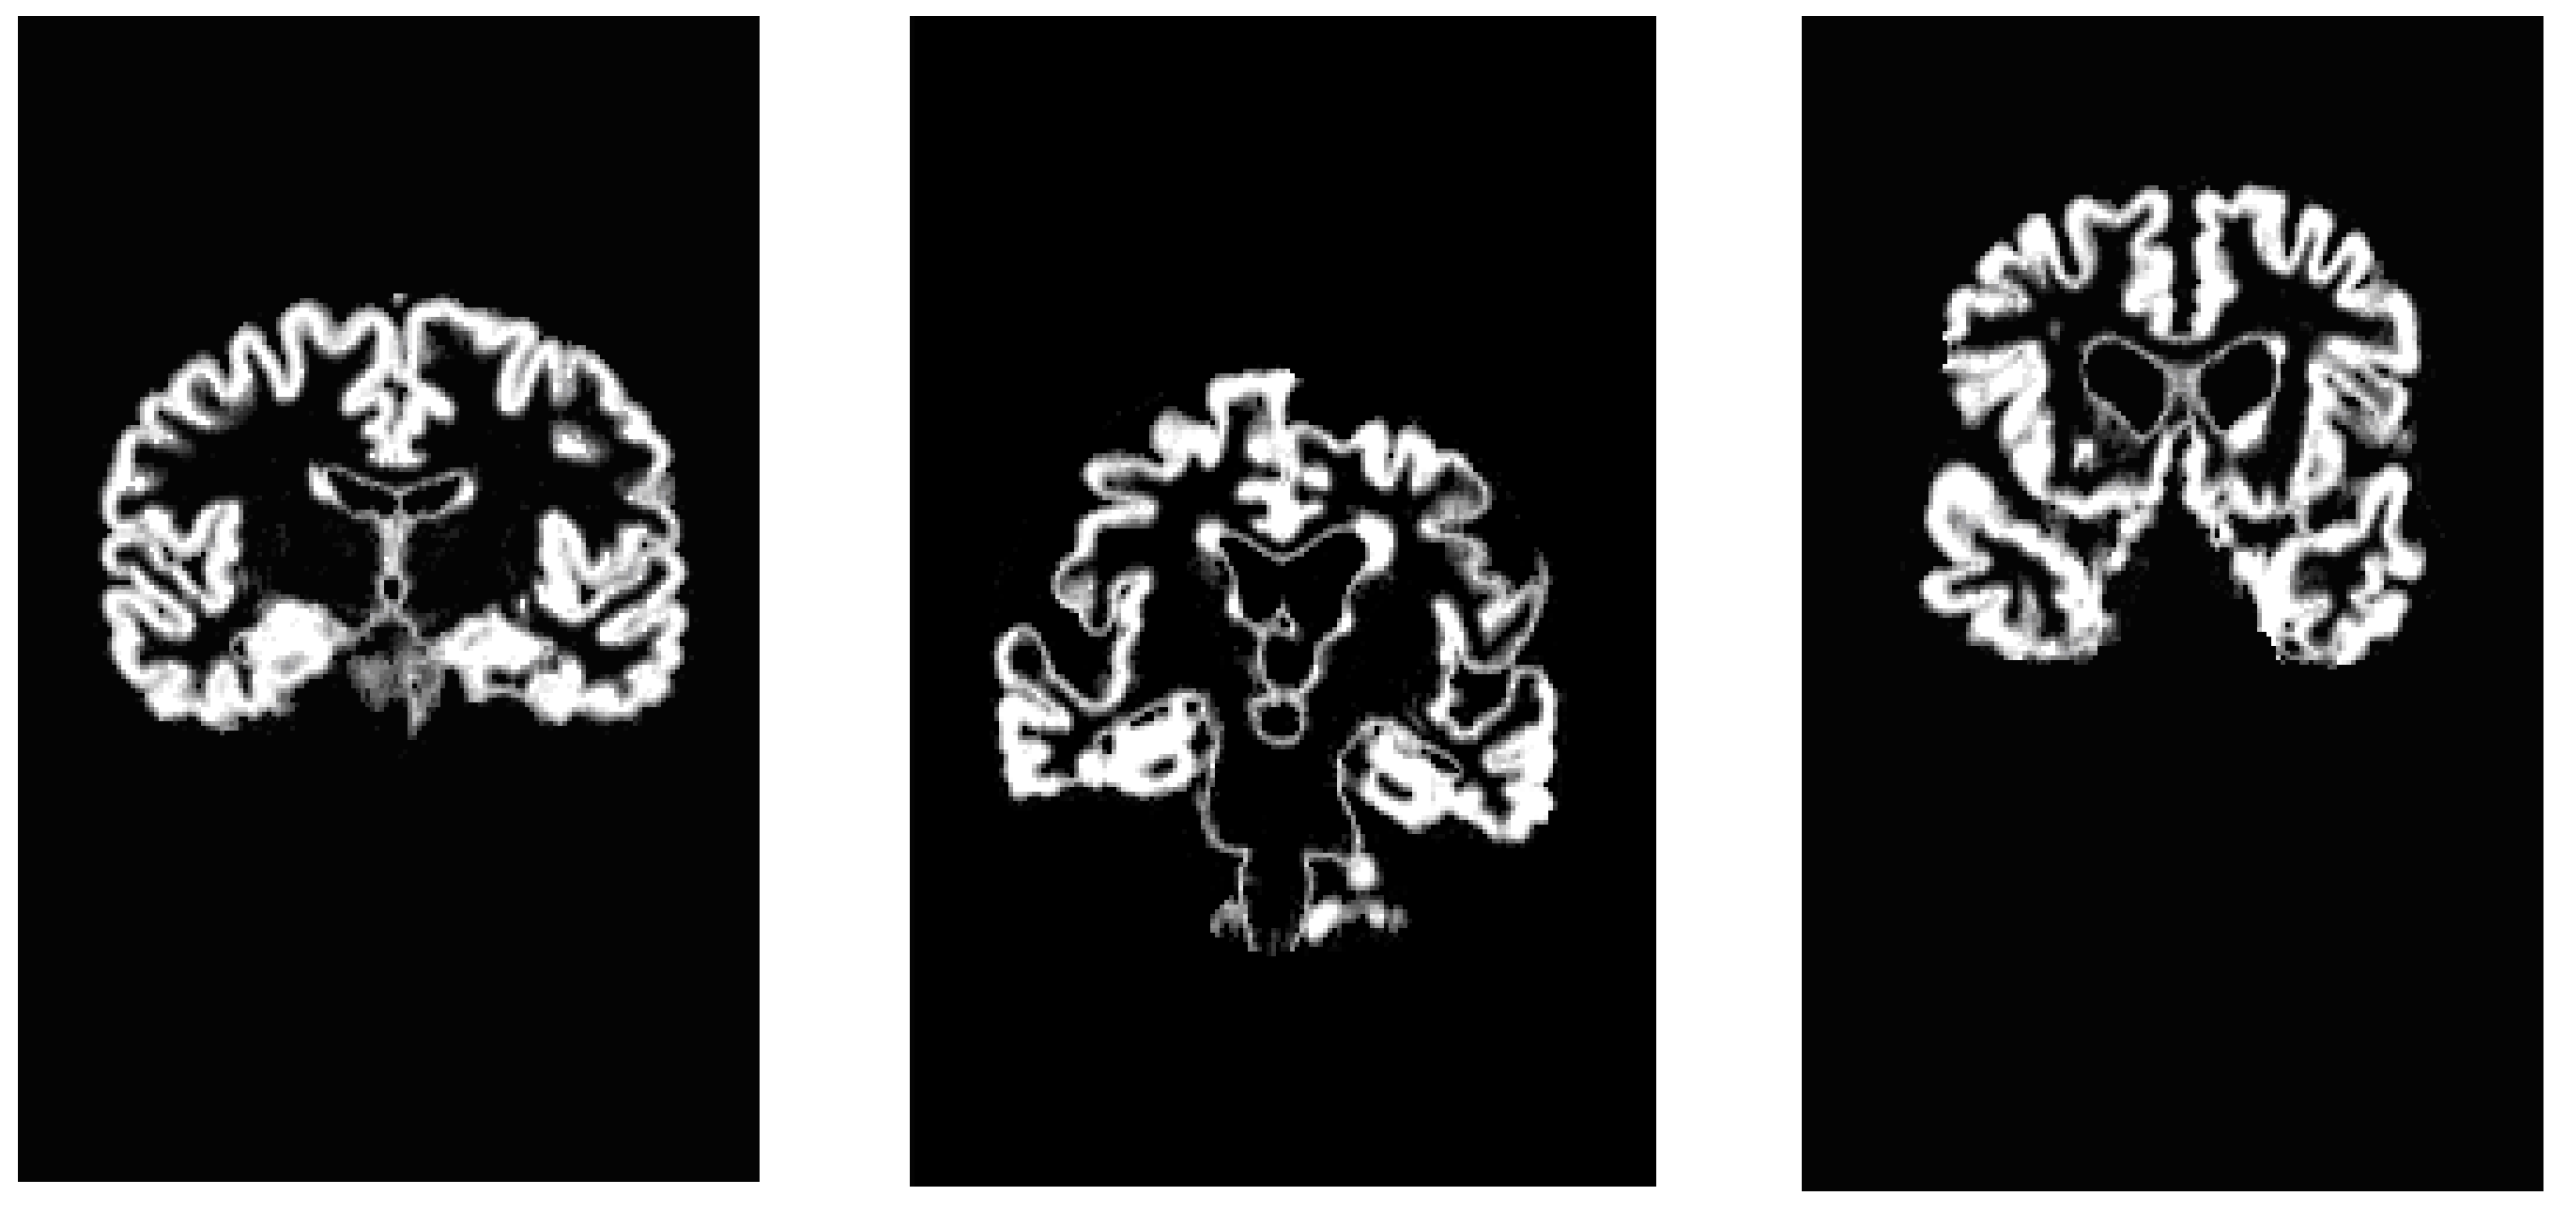

For what concerns DTI images, this approach is addressed to demarcate the areas with higher diffusivity of water molecules. We could note the high level of noise present in them; in order to perform a noise reduction, images are initially pre-processed applying a median digital filter (Figure 16). As previously mentioned, the most significant information of a grayscale FA map are taken from zones with high intensity levels corresponding to preferential directions of water diffusion, presumably along axonal bundles. Thus after analyzing the intensity distribution of image pixels (Figure 17 and Figure 18), we have obtained an image segmentation by using thresholds ranging from 180 to 210. Subsequently, edge extraction has been performed through an automatic selection of an initial contour from the level curves of the divergence map (Figure 18, Figure 19 and Figure 20).

Figure 16. (a) DTI image for a non-pathological subject; (b) Filtered FA map.

Algorithms 05 00636 g016

Figure 17. Intensity distribution of image pixels for a FA map.

Algorithms 05 00636 g017

Figure 18. DTI image extraction for a non-pathological subject.

Algorithms 05 00636 g018